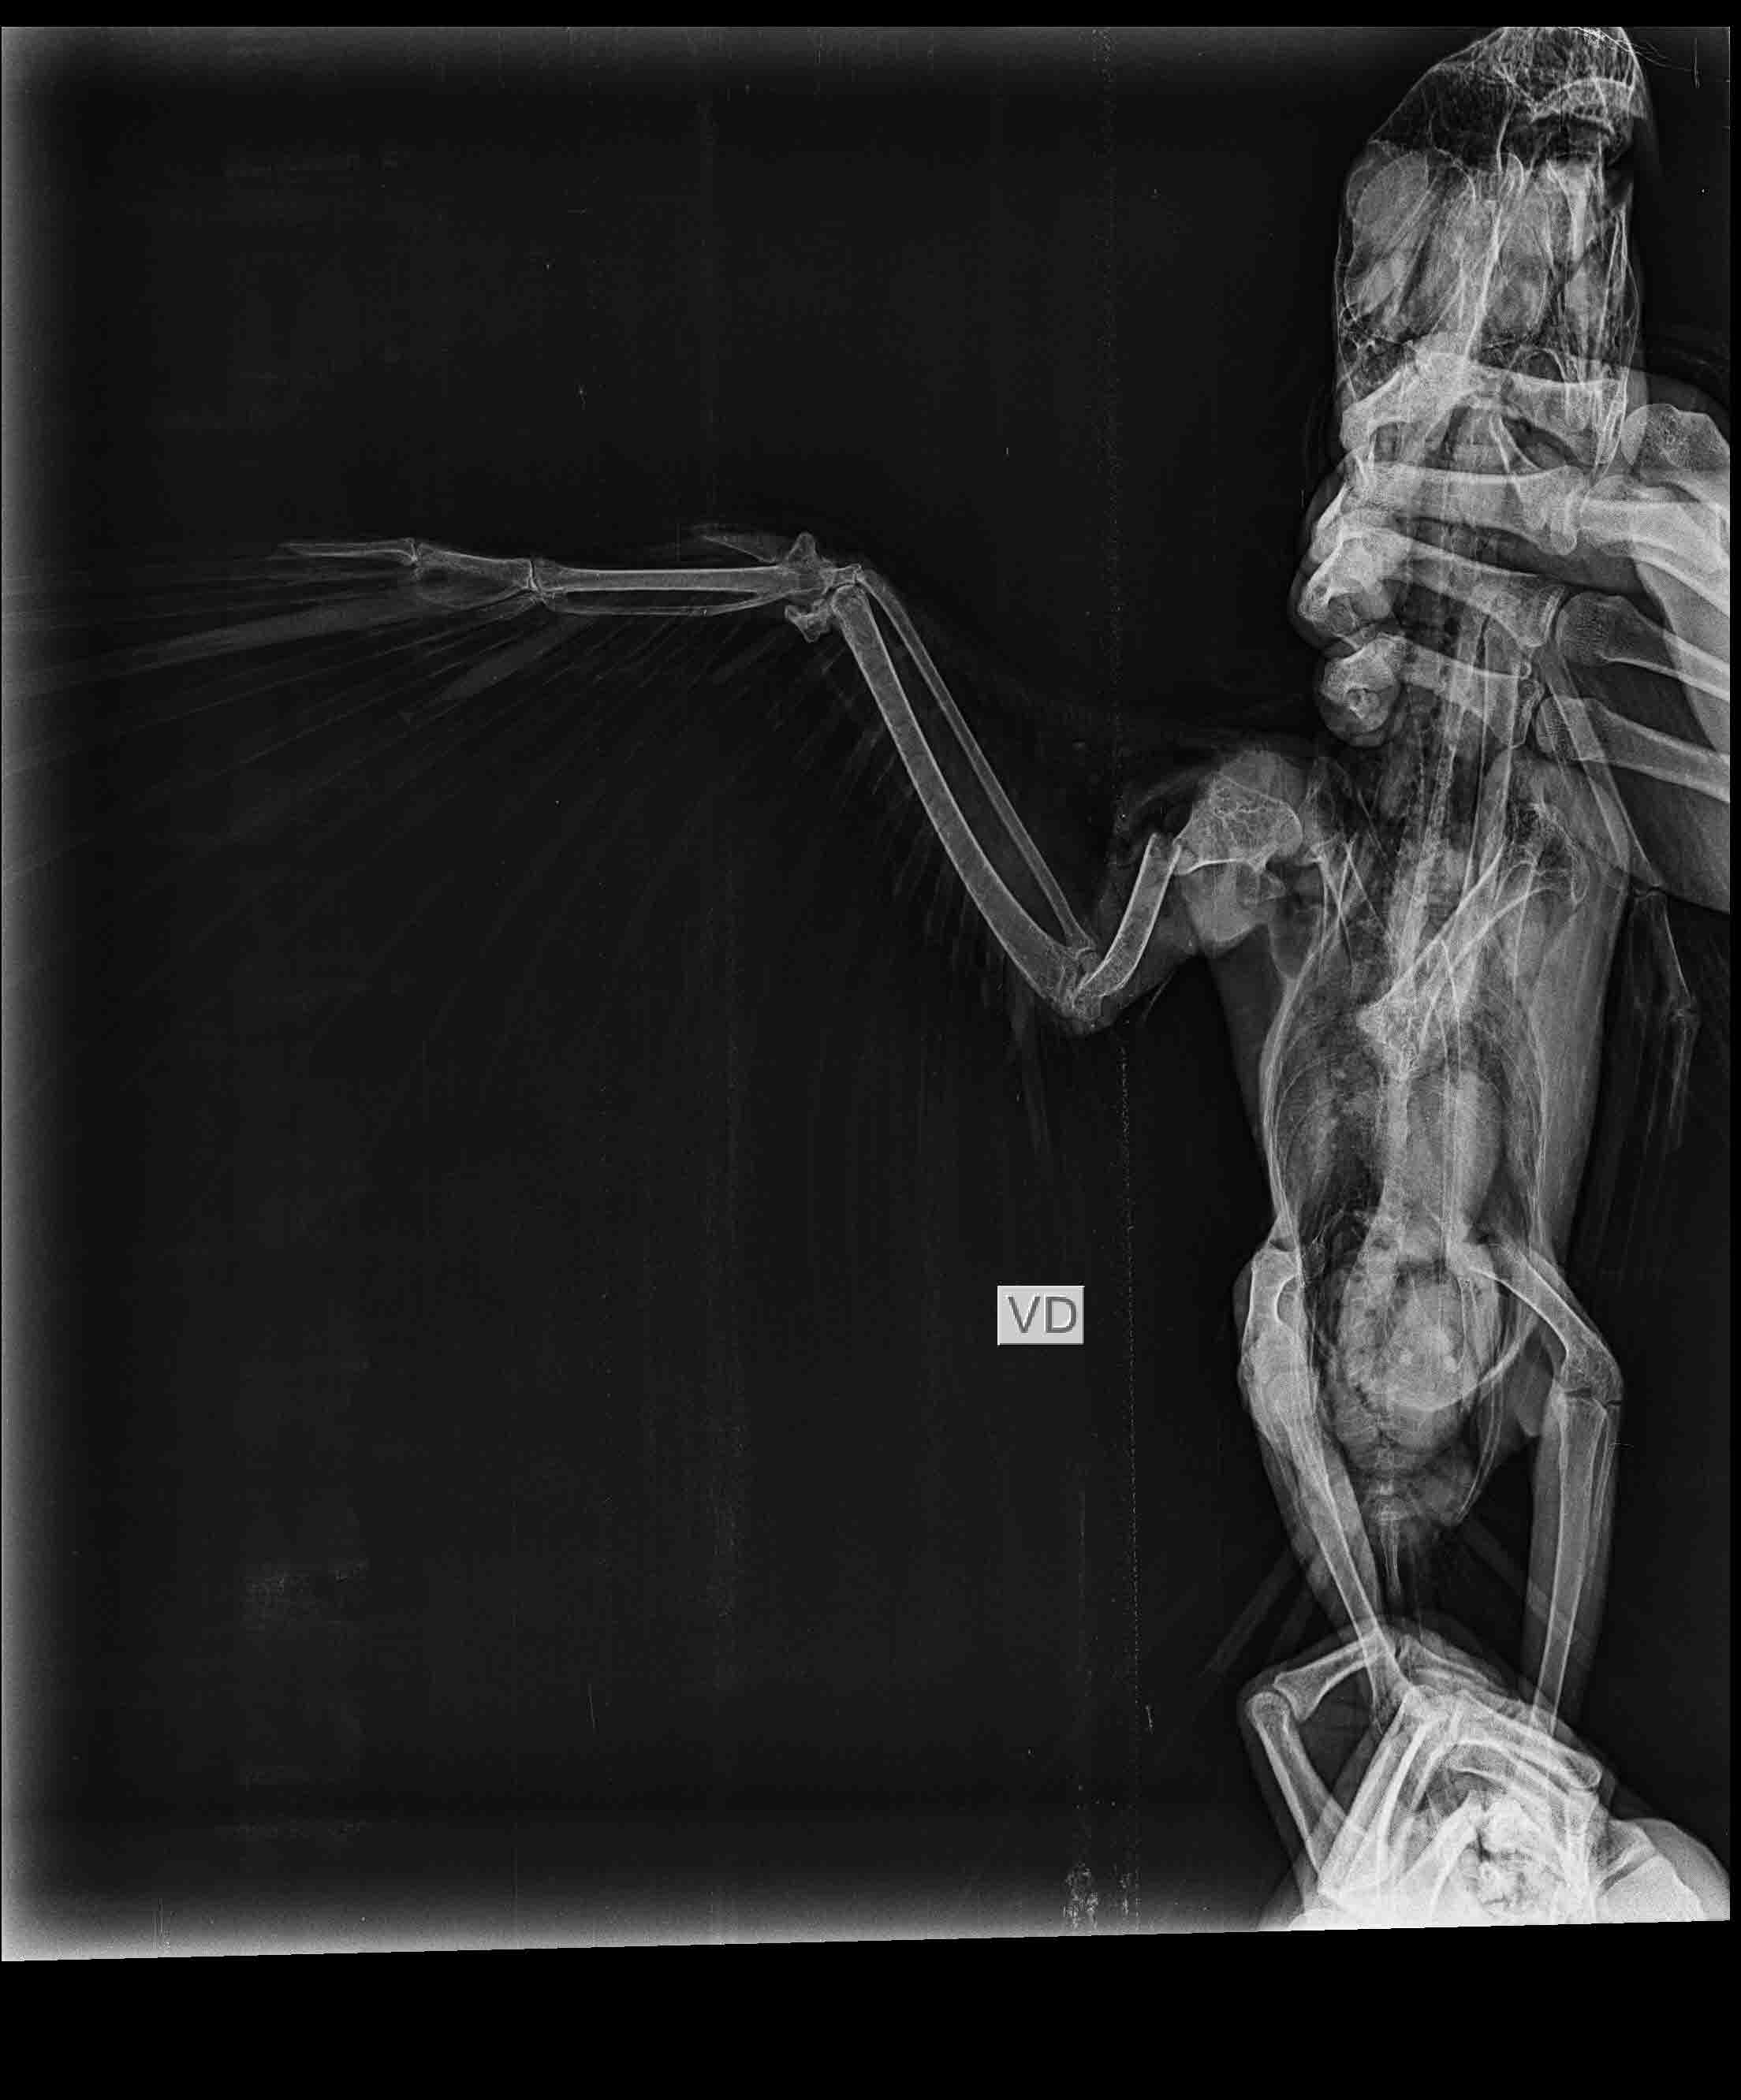

“Assim que constatamos a fratura em asa, o animal passou por um processo de estabilização com bandagem e ficou no aguardo do procedimento cirúrgico. Entramos em contato com a Clínica Dupet, que prontamente aceitou a parceria, e, assim, conseguimos marcar uma cirurgia de Osteossíntese de Úmero, com a parceria do Dr. Plínio Montalvani. Graças à eficiência de toda a equipe que participou, o procedimento cirúrgico na arara-azul-de-lear foi um sucesso”, explica Márcio, que também é médico veterinário do Inema.